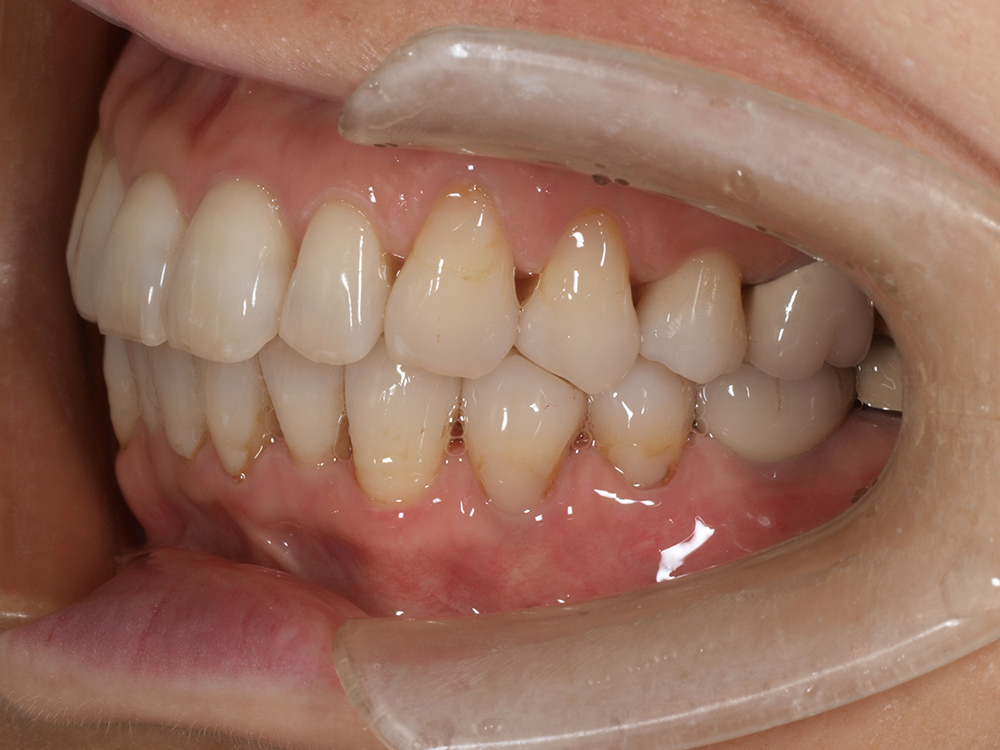

58歳 男性 歯科医療関係者紹介

- 主訴

- 右下を抜歯して噛めない

- 処置内容

- インプラント2本埋入

- 治療費用

- 約80万円(税込)

- 治療期間

-

8か月

仮歯完成まで5か月(この時点で噛めます)、+3か月で最終素材へ

- リスク

- 上部構造物、仮歯の破折、術後の腫れ(3日)、人工歯根脱落リスクがあります